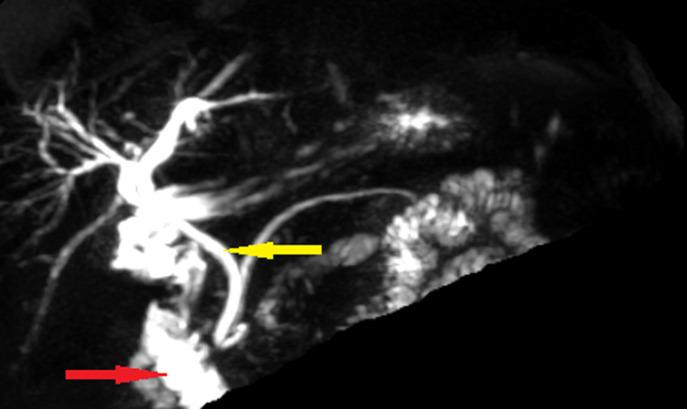

Gallbladder agenesis (GA) is a rare congenital malformation characterized by the absence of the gallbladder and cystic duct due to an anomaly in the embryonic development. It is commonly associated with other congenital abnormalities, and the isolated form is extremely rare. Its clinical presentation is variable. Actually, GA is more often incidentally diagnosed. Magnetic resonance cholangiopancreatography (MRCP) is considered to be the diagnosis method of choice since it avoids unnecessary and risky surgery in symptomatic patients. Here we report the case of a radiologically incidentally discovered gallbladder agenesis in a 68-year-old patient.

胆囊发育不全(GA)是一种罕见的先天性畸形,其特征为胆囊和胆囊管缺失,这是由于胚胎发育异常所致。它通常与其他先天性异常有关,而孤立型极为罕见。其临床表现多种多样。实际上,GA 更多是偶然诊断出来的。磁共振胆胰管成像(MRCP)被认为是首选的诊断方法,因为它避免了有症状的患者进行不必要且有风险的手术。在此,我们报告了 1 例 68 岁患者经影像学偶然发现的胆囊发育不全。